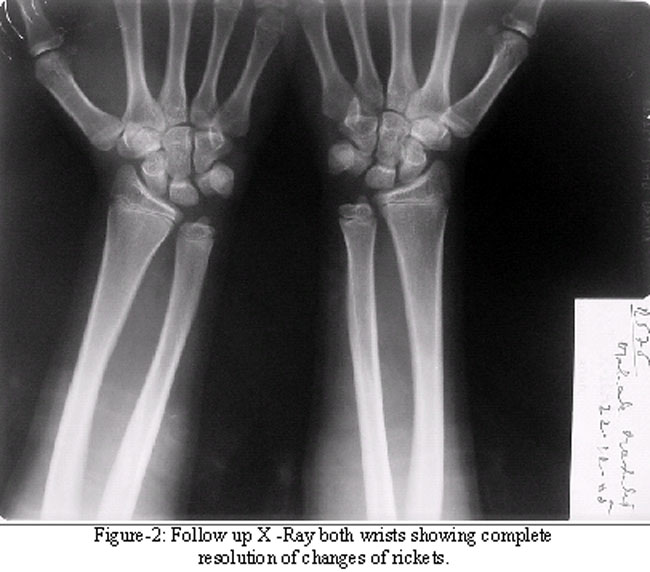

A -15-year girl was evaluated at the age of 5 years for lower limb deformities. She was the second child of her non consanguineous parents, was born full term and had no perinatal insult. She had been weaned at appropriate age and had a normal physical and mental development. At age 4 years; her parents noticed deformities in her lower limbs. The child was diagnosed to have rickets and treated with 3.6 million units of vitamin D (six lac units weekly intramuscularly over a period of six weeks). There was no clinical or radiological evidence of improvement over the next one year. She was referred to the endocrinology for further evaluation. Examination revealed height of 105 cms [50th percentile by Indian Council of Medical Research (ICMR) standards] with upper segment to lower segment ratio of 1:1 and weight of 17 Kgs (50th percentile by ICMR standards). She had signs of rickets in the form of widening of wrists, rachitic rosary and knock knees. Investigations revealed normal complete blood count (CBC), liver and kidney functions. Bone function tests revealed a serum calcium of 8.9 mgs/dl, (normal value of 9.5-11.5mgs/dl), phosphorus of 4.3 mgs/dl (normal value of 5-7mgs/dl for her age) and alkaline phosphatase of 611U/L (normal value 30-120 in adults). X-ray wrist revealed changes of rickets (Figure-1), Pelvic x-ray revealed looser, s zones in superior and inferior pubic ramie. She was evaluated for non nutritional rickets. She had no evidence of renal tubular acidosis or Fanconi syndrome. Serum 25- hydroxy vitamin D was 100 ng/ml (normal value 8-80), 1, 25 dihydroxy vitamin D was less than 5 pg/ml (normal value16-65). Serum concentrations of 25-hydroxy vitamin D and 1, 25 dihydroxy vitamin D were measured by specific radioimmunoassay. In view of clinical and radiological evidence of rickets, no response to massive doses of vitamin D, high Serum 25- hydroxy vitamin D and undetectable 1, 25 dihydroxy vitamin D a diagnosis of pseudo vitamin D deficiency rickets was made. She was started on calcitriol 0.25 g/day and elemental calcium 500mgs/day. The patient was next seen after four months and had a marked clinical and radiological improvement (Figure-1).

At the age of 11 years dose of calcitriol was increased to 0.5 g/day and calcium to 750mg/day with monitoring of serum calcium every 3-6 months which were within normal limits. Meanwhile the girl attained menarche at the age of 13 years. At the age of 14 years she developed left flank pain and haematuria. Ultrasonography revealed multiple stones biggest being around 0.87×0.79mm in right middle and lower calyces without any hydronephrosis (Figure-2).